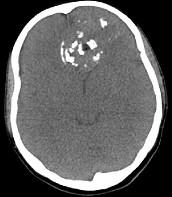

问题 男性,28岁,因鼻塞、头痛1年余,鼻窦CT扫描如图所示,请选择正确的描述与结论()

选项 A.双侧上颌窦、筛窦、鼻腔及蝶窦内见软组织肿块影 B.肿块内密度不均,有较多致密钙化影 C.窦壁及颅底骨质破坏 D.考虑鼻窦骨瘤 E.考虑为鼻窦软骨瘤

答案 ABCE